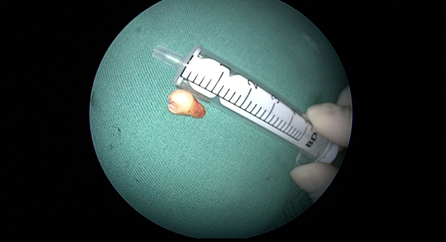

近日(ri),耳鼻喉科(ke)成(cheng)功開展(zhan)1例鼻內(nei)鏡下含牙囊腫切除術(shù)。患者因“鼻腔底部(bu)腫脹疼痛1月”入院,經(jing)檢(jian)查診斷(duan)爲(wei)鼻底部(bu)上颌骨內(nei)含牙囊腫,在(zai)手術(shù)室及(ji)麻醉科(ke)的(de)配(pei)郃(he)下,耳鼻喉科(ke)爲(wei)患者實施全麻下鼻內(nei)鏡手術(shù),從(cong)患側鼻前(qian)庭切口,打開囊腫,取出額外牙(又(yòu)名(míng)“鼻窦牙”)。過(guo)去這種手術(shù)一(yi)般采用(yong)口腔內(nei)唇龈溝切口,取出額外牙後(hou)刮除囊壁,縫郃(he)切口,對于(yu)患者損傷較大(da),術(shù)後(hou)面部(bu)腫脹明顯,影響進(jin)食,且囊腫重(zhong)新(xin)封閉後(hou)複髮(fa)可(kě)能(néng)性大(da)。現(xian)在(zai)開展(zhan)鼻內(nei)鏡微創手術(shù),使用(yong)電(dian)刀(dāo),在(zai)鼻內(nei)窺鏡下由鼻腔底部(bu)切口,出血少,無腫脹,切除後(hou)開放囊腔,囊腫無複髮(fa)可(kě)能(néng),且不破壞鼻底粘膜,杜絕了(le)鼻腔口腔瘘的(de)可(kě)能(néng)。(耳鼻喉科(ke))